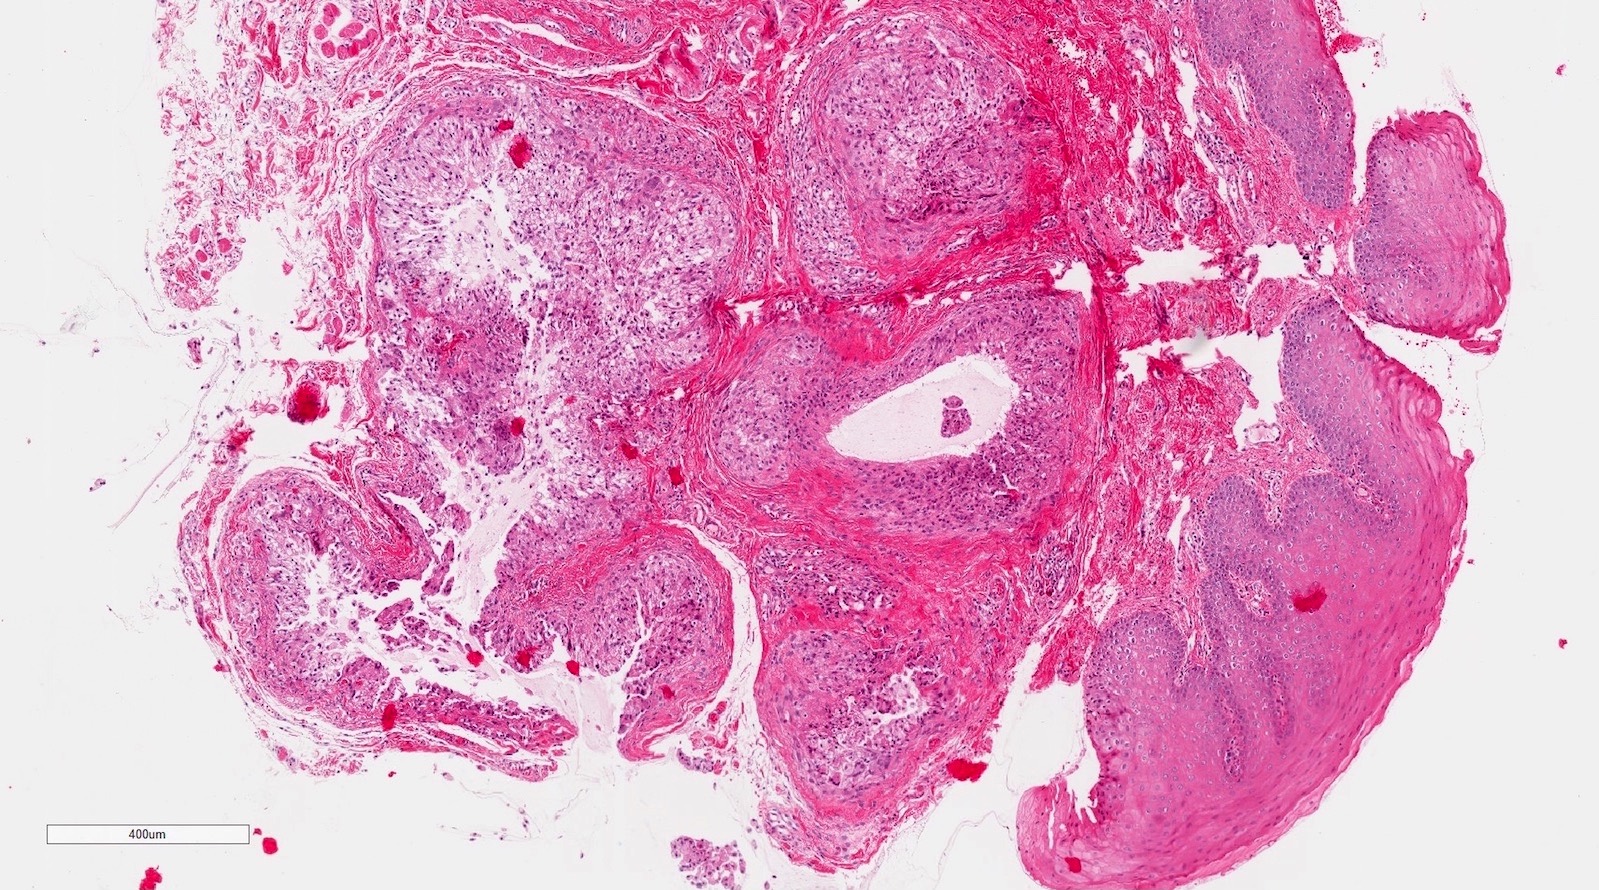

Microscopic (histologic) description

- If removed intact

- Pseudocyst cavity containing mucin, abundant epithelioid foamy histiocytes (muciphages), neutrophils and granulation tissue (Acta Histochem 2014;116:40)

- If removed ruptured

- Fragments of granulation tissue containing epithelioid foamy histiocytes (muciphages) and neutrophils, may see mucinous material (Acta Histochem 2014;116:40)

- Removed salivary gland parenchyma showing obstructive changes

- Acinar atrophy, ductal dilatation with periductal hyalinization, interstitial lymphoplasmacytic infiltrate and interstitial fibrosis at late stage (J Oral Maxillofac Surg 2008;66:2050)

- May see ruptured feeding salivary duct with squamous metaplasia (J Oral Maxillofac Surg 2008;66:2050)

- Long standing lesions organize into fibrosis resembling a fibroepithelial polyp (Acta Histochem 2014;116:40)

- No epithelial cyst lining, may see overlying surface oral mucosa with variable atrophy in superficial mucoceles (J Oral Maxillofac Surg 2011;69:1086)

Microscopic (histologic) images